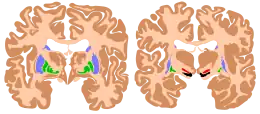

Les ganglions de la base (autrement appelés noyaux gris centraux ou noyaux de la base) sont un ensemble de structures sous-corticales constitué par des noyaux pairs, interconnectés au niveau télencéphalique (hémisphères cérébraux) et diencéphalique. Leur structure peut varier selon qu'on les définit de manière anatomique ou fonctionnelle[1].

Au sens purement anatomique ils comprennent quatre noyaux pairs :

- le noyau caudé ;

- le noyau lenticulaire correspondant au putamen et au pallidum ;

- le noyau sous-thalamique ;

- la substance noire.

Au sens fonctionnel, on aborde ces structures de manière différente :

- le striatum composé du noyau caudé et du putamen (correspondant à la partie latérale du noyau lenticulaire) ;

- le globus pallidus interne (GPi) et le globus pallidus externe (GPe), correspondant au pallidum (partie médiale du noyau lenticulaire) ;

- le noyau sous-thalamique (ou corps de Luys) ;

- la substance noire compacte (SNpc, du latin : substantia nigra pars compacta), et la substance noire réticulée (SNr, substantia nigra pars reticulata).